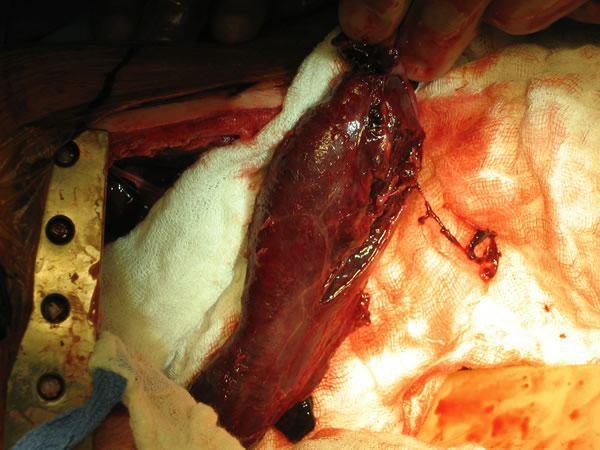

In the operating room, a right thoracotomy through the 5th intercostal space, 5th rib resection, and an intercostal muscle flap harvest was performed. Upon entering the chest, a large abscess was present surrounding the distal esophagus, with an empyema and widespread posterior mediastinitis. The esophagus exhibited full-thickness necrosis extending from the gastroesophageal junction to 5 cm below the thoracic inlet and was filled with clotted blood. There was a perforation of the distal esophagus extending from 10cm below the carina to the gastroesophageal junction (Figures 3A&B). The esophagus was resected with proximal and distal transections completed with an endoGIA 45 (3.5mm) stapling device. The posterior mediastinum was debrided and the right lung decorticated. Three chest tubes were placed, and a naso-gastric tube was placed within the cervical esophagus and both jejunostomy and gastrostomy tubes were placed. Forty eight hours later and off pressors, the patient was taken to the operating room for creation of a left cervical esophagostomy.